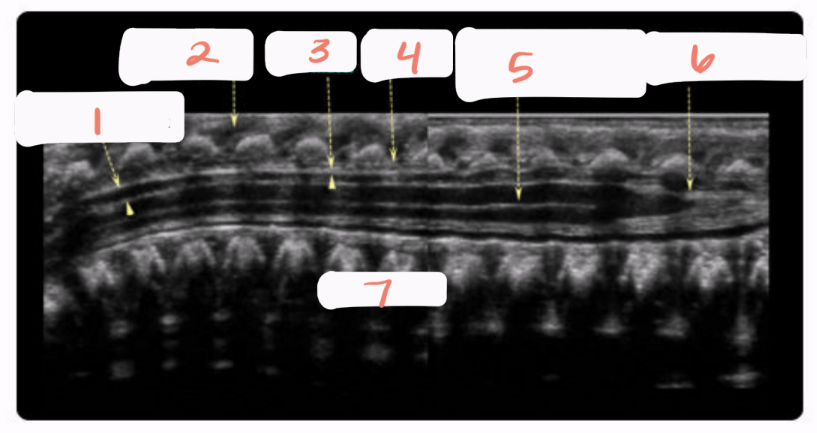

1

subarachnoid space

2

cartilaginous spinous processes

3

dura mater

4

epidural space

5

central echo complex in hypoechoic spinal cord

6

conus medullaris

7

vertebral bodies